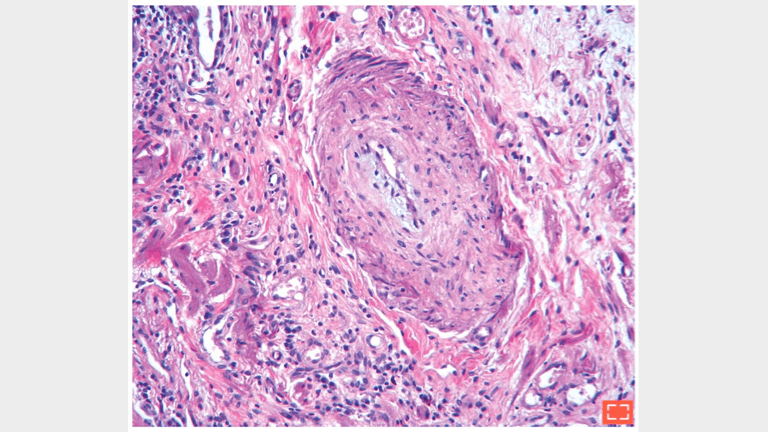

• Reductions of the vascular lumen

• Marked intimal and medial hyperplasia in this artery

• Sometimes complete luminal occlusion

Hypertensive arterial lesion.

Reduction of the vascular lumen in fibrotic area.